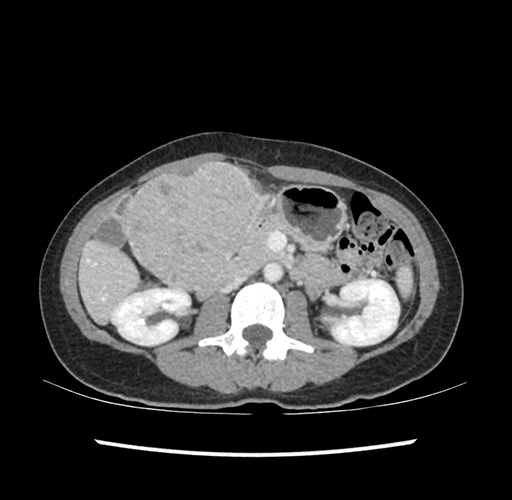

Imaging Analysis

Look through the patient's CT scan to identify any areas of concern for the necessary procedure.

Based on your CT findings, which issue(s) would give reason for "planned slowing down moment(s)" in this case?